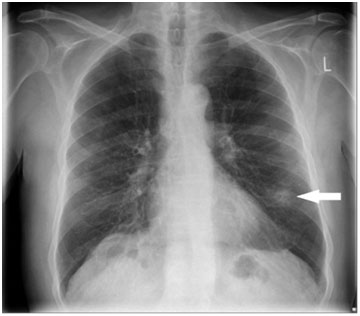

圖片來源BMJ

Kanaan博士:從定義上看,肺結(jié)節(jié)是指直徑在3厘米以內(nèi)的類圓形或不規(guī)則型病灶,而大于3厘米的病灶則稱為肺腫塊。在成像測試描述中,肺結(jié)節(jié)通常被稱為“硬幣病灶”。其中,磨玻璃樣結(jié)節(jié)(GGO)是較多發(fā)生在亞洲人群的一種結(jié)節(jié)形態(tài),表現(xiàn)為密度輕度增高但又沒有遮住支氣管血管,仿佛在肺部組織上蒙上了片磨玻璃的云霧狀淡薄影/圓形結(jié)節(jié)。